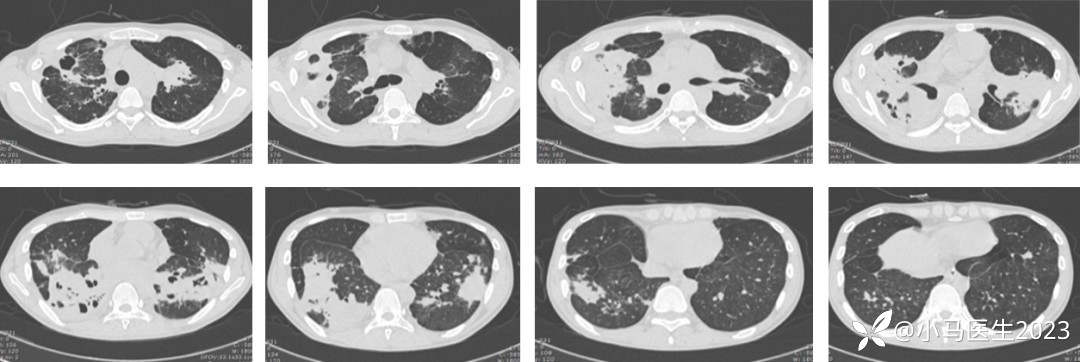

04-06 胸部CT仍进展

2021-04-28胸部CT进展,空洞形成

胸部CT对比